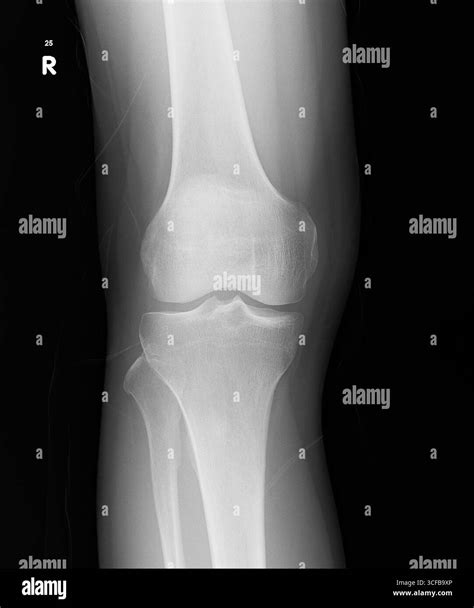

• Imaging Tests: X-rays are the baseline, but an ultrasound or MRI is far more effective at detecting a small joint effusion because these methods can visualize soft tissues and identify fluid pockets that X-rays might miss.

• small joint effusion knee treatment